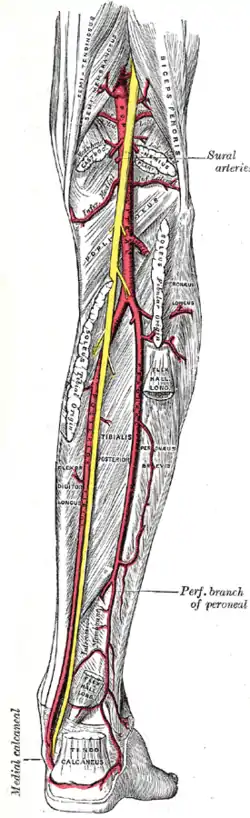

The arteries of the leg are divided into a series of segments.

In the pelvis area, at the level of the last lumbar vertebra, the abdominal aorta, a continuation the descending aorta, splits into a pair of common iliac arteries. These immediately split into the internal and external iliac arteries, the latter of which descends along the medial border of the psoas major to exits the pelvis area through the vascular lacuna under the inguinal ligament.[42]

The artery enters the thigh as the femoral artery which descends the medial side of the thigh to the adductor canal. The canal passes from the anterior to the posterior side of the limb where the artery leaves through the adductor hiatus and becomes the popliteal artery. On the back of the knee the popliteal artery runs through the popliteal fossa to the popliteal muscle where it divides into anterior and posterior tibial arteries.[42]

In the lower leg, the anterior tibial enters the extensor compartment near the upper border of the interosseus membrane to descend between the tibialis anterior and the extensor hallucis longus. Distal to the superior and extensor retinacula of the foot it becomes the dorsal artery of the foot. The posterior tibial forms a direct continuation of the popliteal artery which enters the flexor compartment of the lower leg to descend behind the medial malleolus where it divides into the medial and lateral plantar arteries, of which the posterior branch gives rise to the fibular artery.[42]

Small saphenous vein and its tributaries The popliteal, posterior tibial, and peroneal arteries

The popliteal, posterior tibial, and peroneal arteries Nerves of the right lower extremity, posterior view